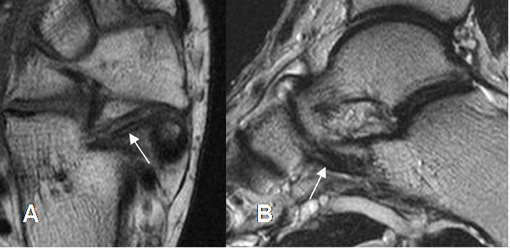

Fig 17. Ligamento calcaneoescafoideo.

A: RM axial en T1 y B: RM sagital en T2. Ligamento hipointenso normal, entre el escafoides y el calcáneo.